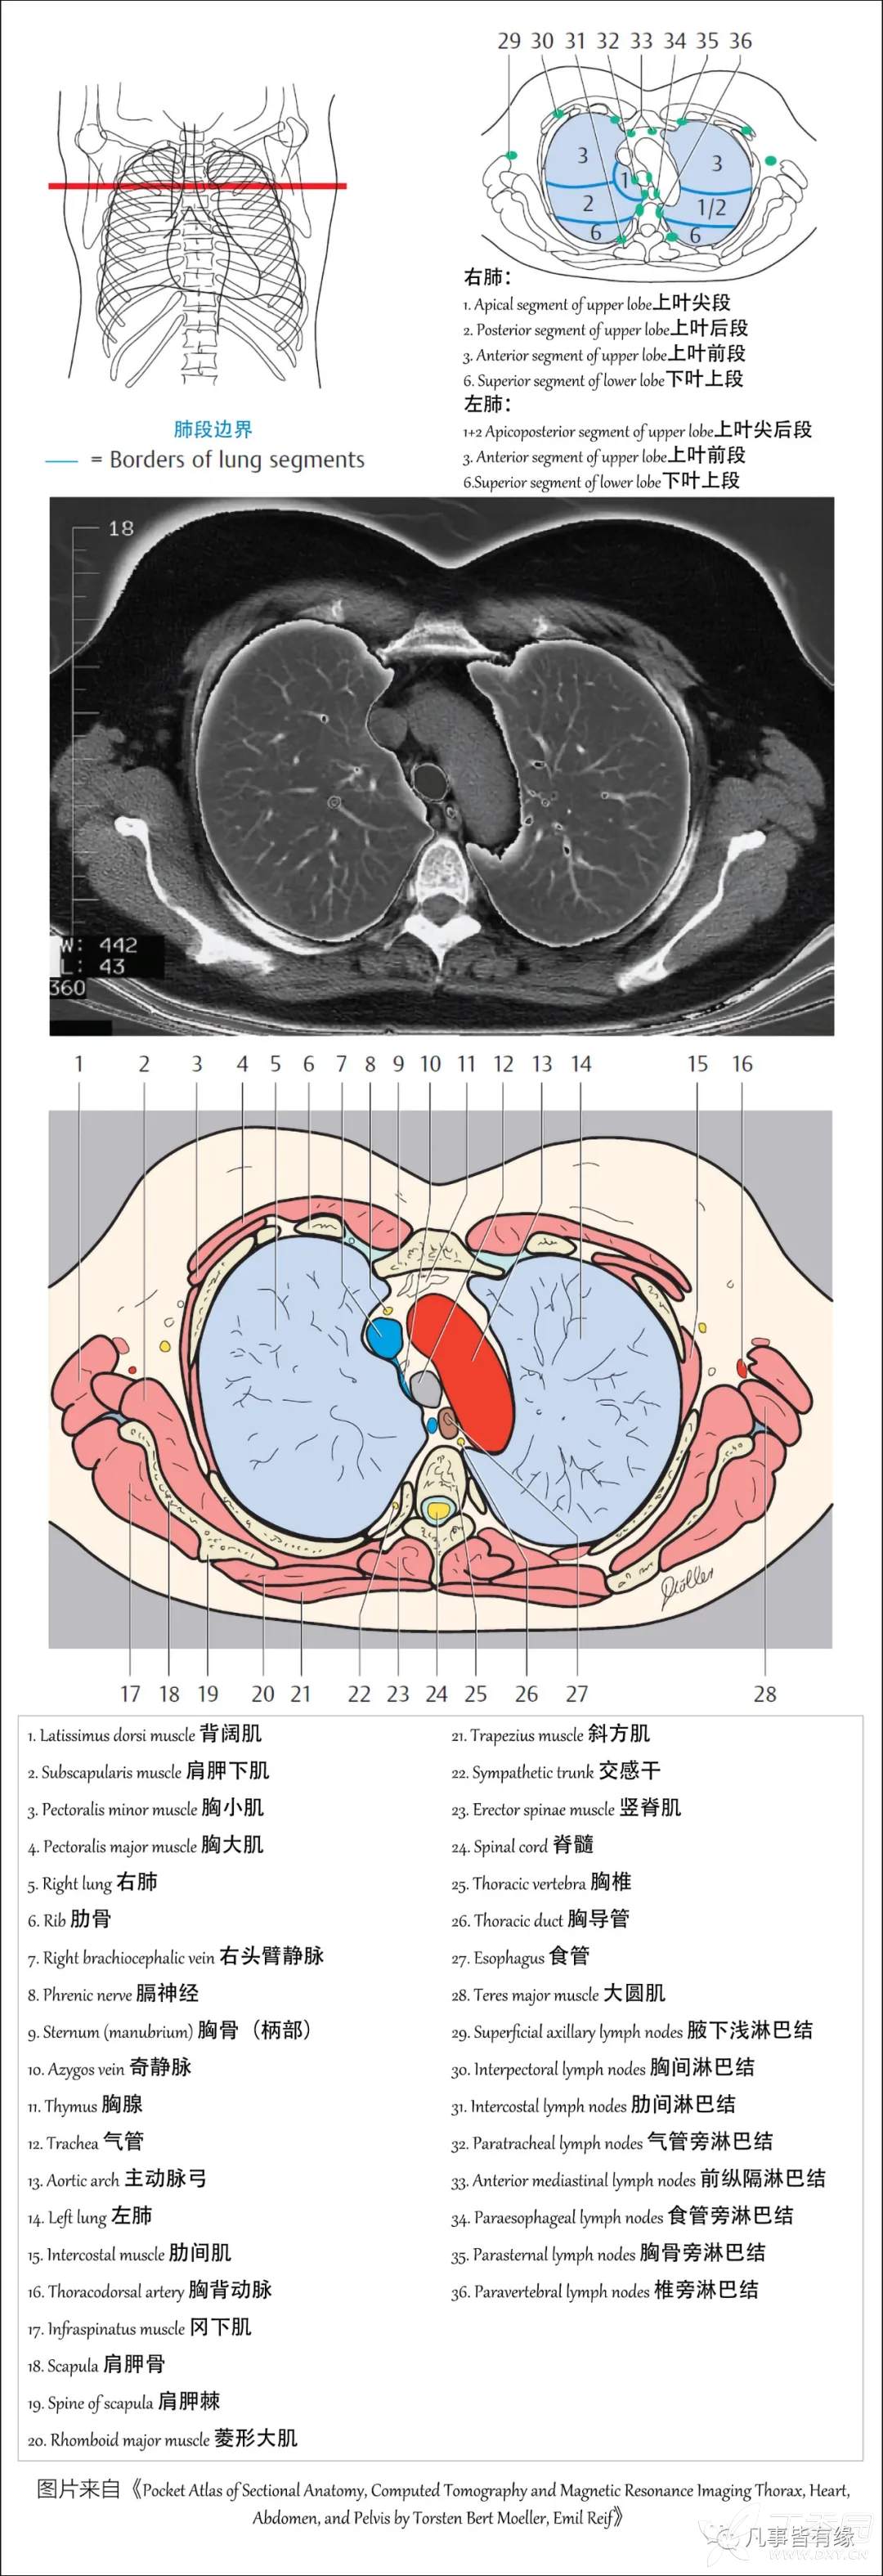

(一)胸部CT轴位断层解剖:

右肺(RightLung)

1.Apical segment of upper lobe 上叶尖段

2.Posterior segment of upper lobe 上叶后段

3.Anterior segment of upper lobe 上叶前段

6.Superior segment of lower lobe 下叶上段

左肺(LeftLung)

1+2Apicoposterior segment of upper lobe 上叶尖后段